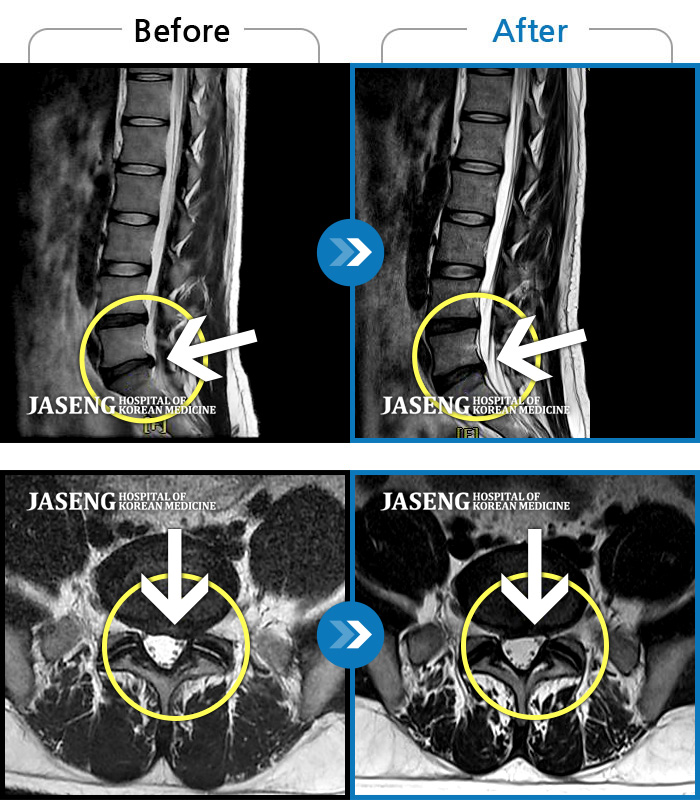

Before

After

환자에게 사전 동의를 받아 동일 조건에서 촬영되었습니다.

개인에 따라 치료 후 부작용이 발생할 수 있으니 의료진과 상담 후 치료를 진행하시기 바랍니다.

수년간 지속되어온 만성적인 허리통증이 최근 들이 치료에도 반응하지 않고 더욱 심해졌다.

재채기 하고 나서 다리에 힘이 안들어가요.